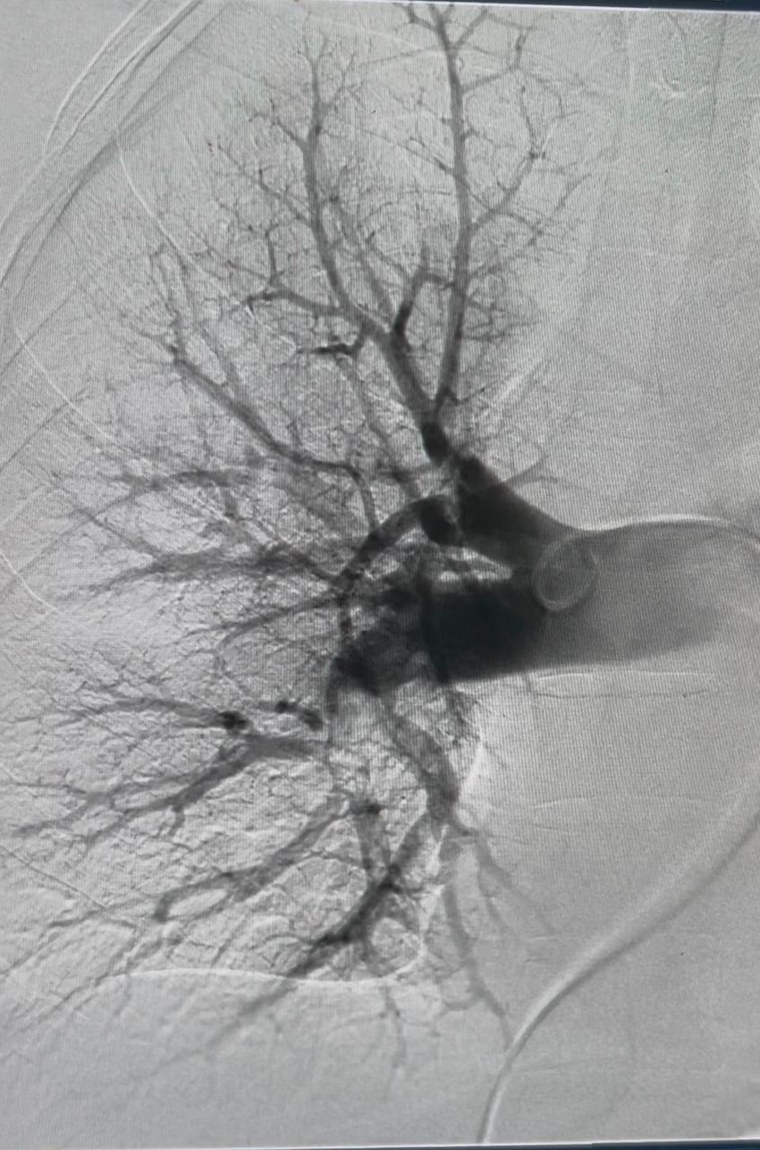

Diagnosticado com trombose pulmonar aguda, o paciente Isaac José de Medeiros, de 48 anos, teve a vida preservada após a realização de uma trombectomia mecânica pulmonar na Hemodinâmica de Patos, serviço instalado no Complexo Hospitalar Regional Deputado Janduhy Carneiro e gerenciado pela Fundação Paraibana de Gestão em Saúde (PB Saúde). O procedimento de alta complexidade foi realizado no último sábado (20) e foi fundamental diante da gravidade do quadro clínico, que apresentava elevado risco de complicações.

Isaac deu entrada na unidade com queixa de dor respiratória e, após avaliação clínica e exames de imagem, foi confirmada a presença de um coágulo de grandes proporções obstruindo a circulação nos vasos do pulmão. A obstrução comprometia o fluxo sanguíneo adequado, o que levou à indicação imediata da trombectomia mecânica pulmonar.

Segundo o cardiologista intervencionista Jean Santiago, a trombectomia mecânica pulmonar consiste na retirada do coágulo de sangue diretamente da artéria pulmonar, permitindo o restabelecimento do fluxo sanguíneo normal. O procedimento foi realizado em caráter de urgência e teve êxito, possibilitando a rápida estabilização do quadro clínico do paciente, que segue em programação de alta hospitalar.